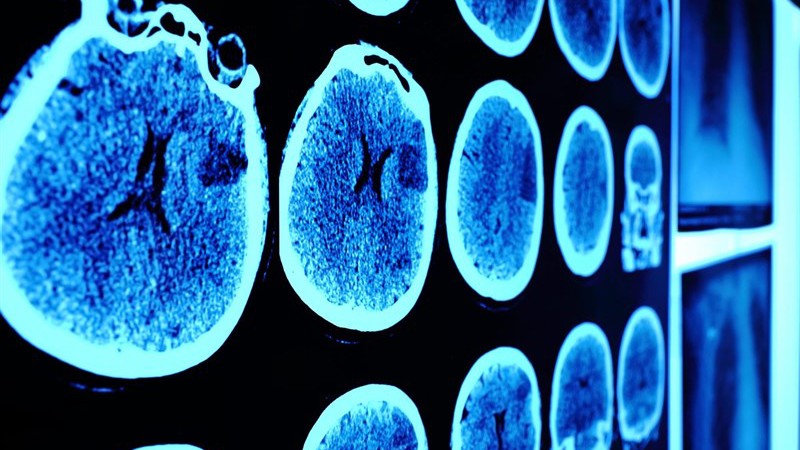

محققان در تصویربرداری عصبی و اسکن توموگرافی کامپیوتری در 120 بیمار از جمله 58 بیمار مبتلا به کووید19 حاد و 62 بیمار بدون ویروس کرونا با سن و جنس متفاوت دریافتند که ماده خاکستری در مبتلایان به ویروس کرونا بیشتر تحت تاثیر قرار میگیرد.